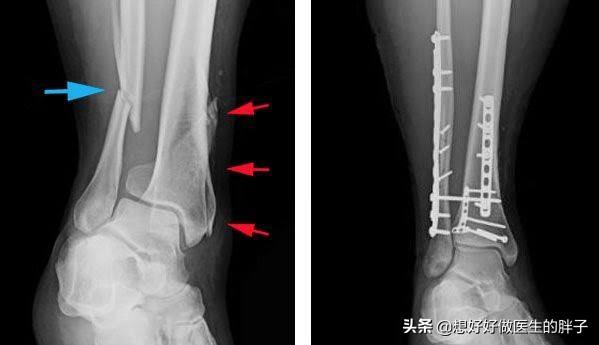

胫腓骨远端粉碎骨折内固定术后

如此复杂的问题,存在的可能性太多问题回答起来比较难,所以我们尽量将问题相对来讲简单化,我们假设患者因为胫腓骨远端粉碎骨折,做了切开复位内固定手术,术后8个月复查骨折愈合比较良好,有轻度的骨质疏松,粘连的是踝关节,那么这种情况应该如何恢复患者的踝关节屈伸角度呢?